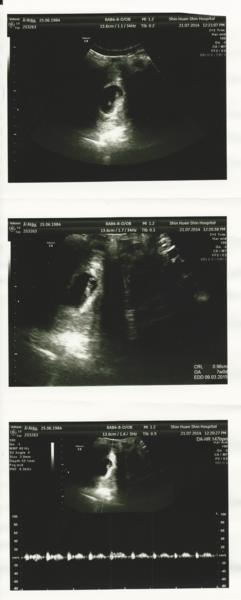

103.07.21

在網路上查了附近婦產科的風評

最後選定馨蕙馨做為日後固定產檢及生產醫院

於是掛了另一個較年輕但風評也不錯的林醫師

林醫師人超親切超nice

照超音波時很仔細地講解

這天超音波就照到寶寶的心跳了

而且還可以聽到心跳聲

當下真的是超感動的~

初步判斷著床位置跟胎盤形狀都良好

子宮也沒有什麼毛病

讓我安心了不少

有趣的是寶寶這時才一公分大

心跳卻很有力地一分鐘跳140多下

老公忍不住開口說: 跳這麼快喔!

林醫師回答心跳代表寶寶很健康

真是讓人開心

這天也領到了媽媽手冊跟做基本檢查(抽血驗尿)

也知道了預產期是明年3/9

會是個雙魚寶寶了